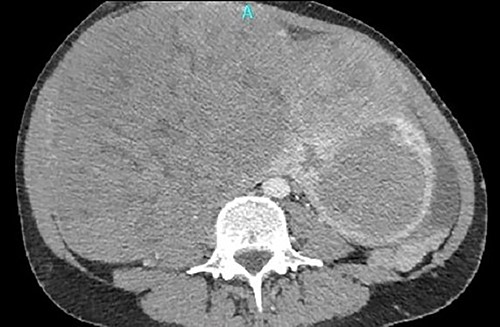

One month later, after vascular consultation, a chest and pelvis computed tomography angiography was performed and a huge mass originating from the uterine wall was revealed (26 cm in diameter) (Fig. 1). The mass compressed the surrounding organs, especially IVC (Fig. 2). Furthermore, thrombosis of left femoral and external and common iliac veins, as well as infrarenal IVC patency (without clarification of IVC thrombosis), was detected. The common, internal and external right iliac veins were patent, and no PE was detected.

Thrombosis of left femoral and external and common iliac veins.